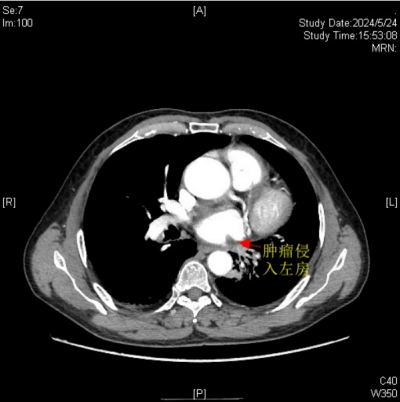

肿瘤侵入左心房

据悉,今年67岁的楚天海(化名)有长达40余年的吸烟史。因反复咳嗽、咯血等症状持续3个月之久,来到91短视频 (南华大学附属长沙中心医院)胸心外科门诊就诊。经全面检查与评估,诊断他患有左肺中央型鳞癌,且肿瘤有部分侵入左心房,情况凶险。

医院胸心外科主任、主任医师袁跃西表示,由于肿瘤侵入左心房,传统手术方式会因为手术视野受限、可能出现难以控制的大出血风险、肿瘤切除可能不彻底及术后恢复难度大等问题,如何确保患者安全并彻底切除肿瘤,成为了摆在医疗团队面前的难题。